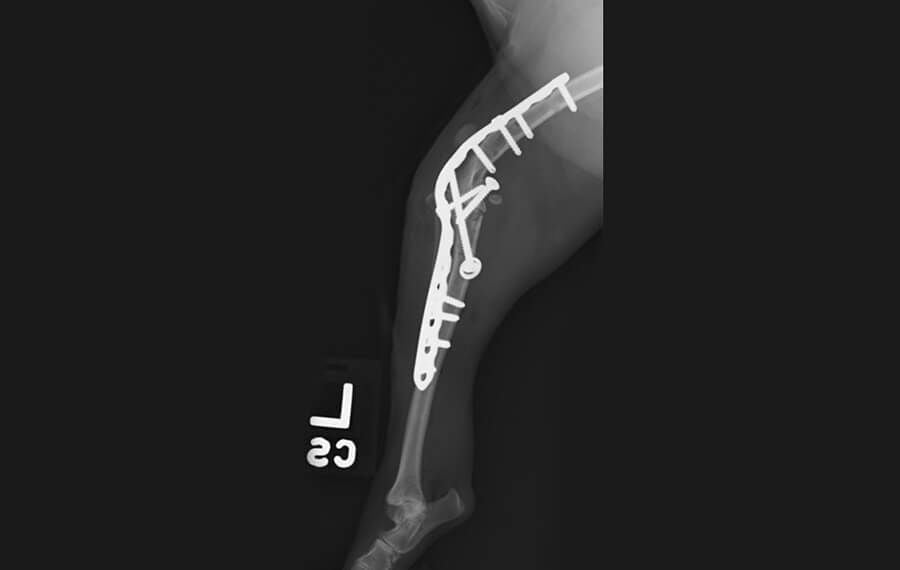

Pancarpal Arthrodesis (fusion of the wrist)

This is the complete fusion of the carpus (the joint between the paw and the elbow). Despite the joint being fused solid, overall limb function usually remains excellent. This is because the shoulder and elbow joints compensate for the lack of movement at the wrist.

- Appearance: To the untrained eye, a dog or cat with a fused carpus will often walk and run normally.

- Common Indications: Most frequently performed for hyperextension injuries (common in active dogs who land awkwardly) and complex fractures of the carpal bones.

Rigid Fixation & Reduced Casting Time

Traditional arthrodesis often required months of heavy, cumbersome casting. At VSS, we use high-strength Specialist Locking Plates that provide extreme mechanical rigidity.

- Earlier Mobility: Because the internal fixation is so stable and the BMP-enhanced healing is so rapid, we can often significantly reduce the time your pet spends in a cast or bandage.

- Superior Comfort: Reducing casting time minimises the risk of "bandage sores," muscle atrophy, and joint stiffness in the rest of the limb, allowing for an earlier and more comfortable transition to physical rehabilitation.